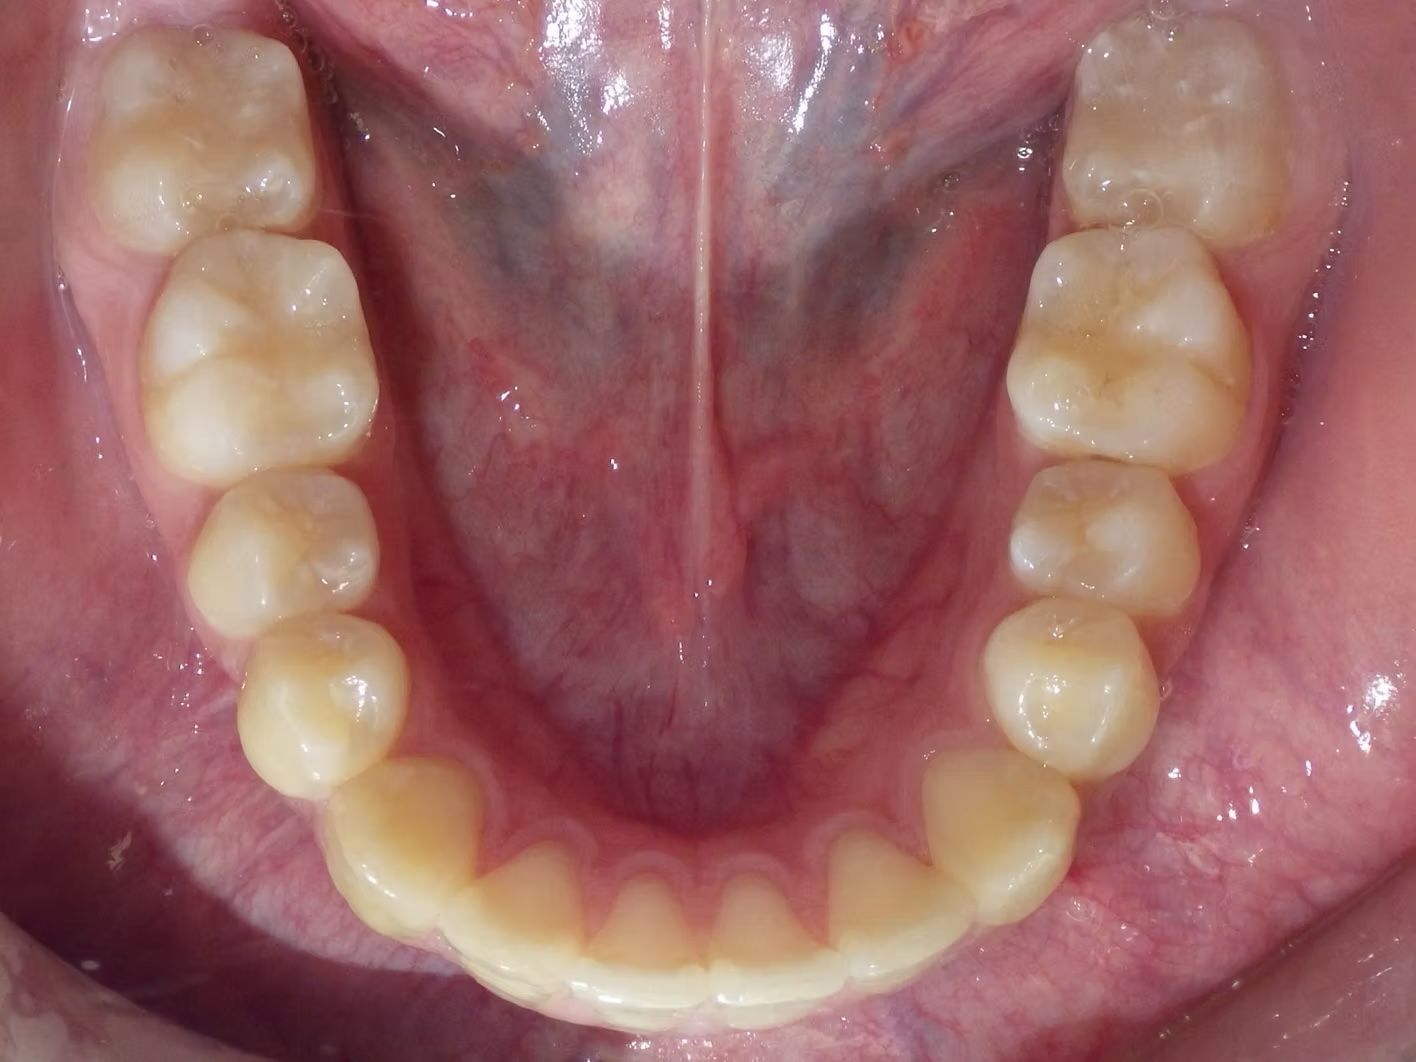

Brianna's lower left 1st premolar was completely in a brodie bite (outside the normal arch) and her top and bottom teeth were very crowded. Dr. Freedman corrected her bite and crowding without removing any teeth.

Click on the images below to enlarge them.